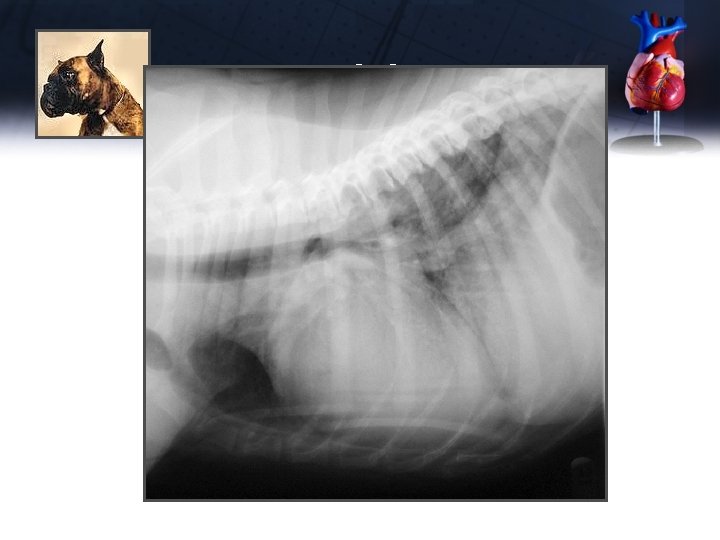

Jake

Jake Diagnostic Plan (B Client) • Chest X-rays – – – Massively enlarged heart (VHS 12. 5) Enlarged LA, LV (dorsally elevated trachea) Enlarged pulmonary veins Perihilar pulmonary edema Left congestive heart failure